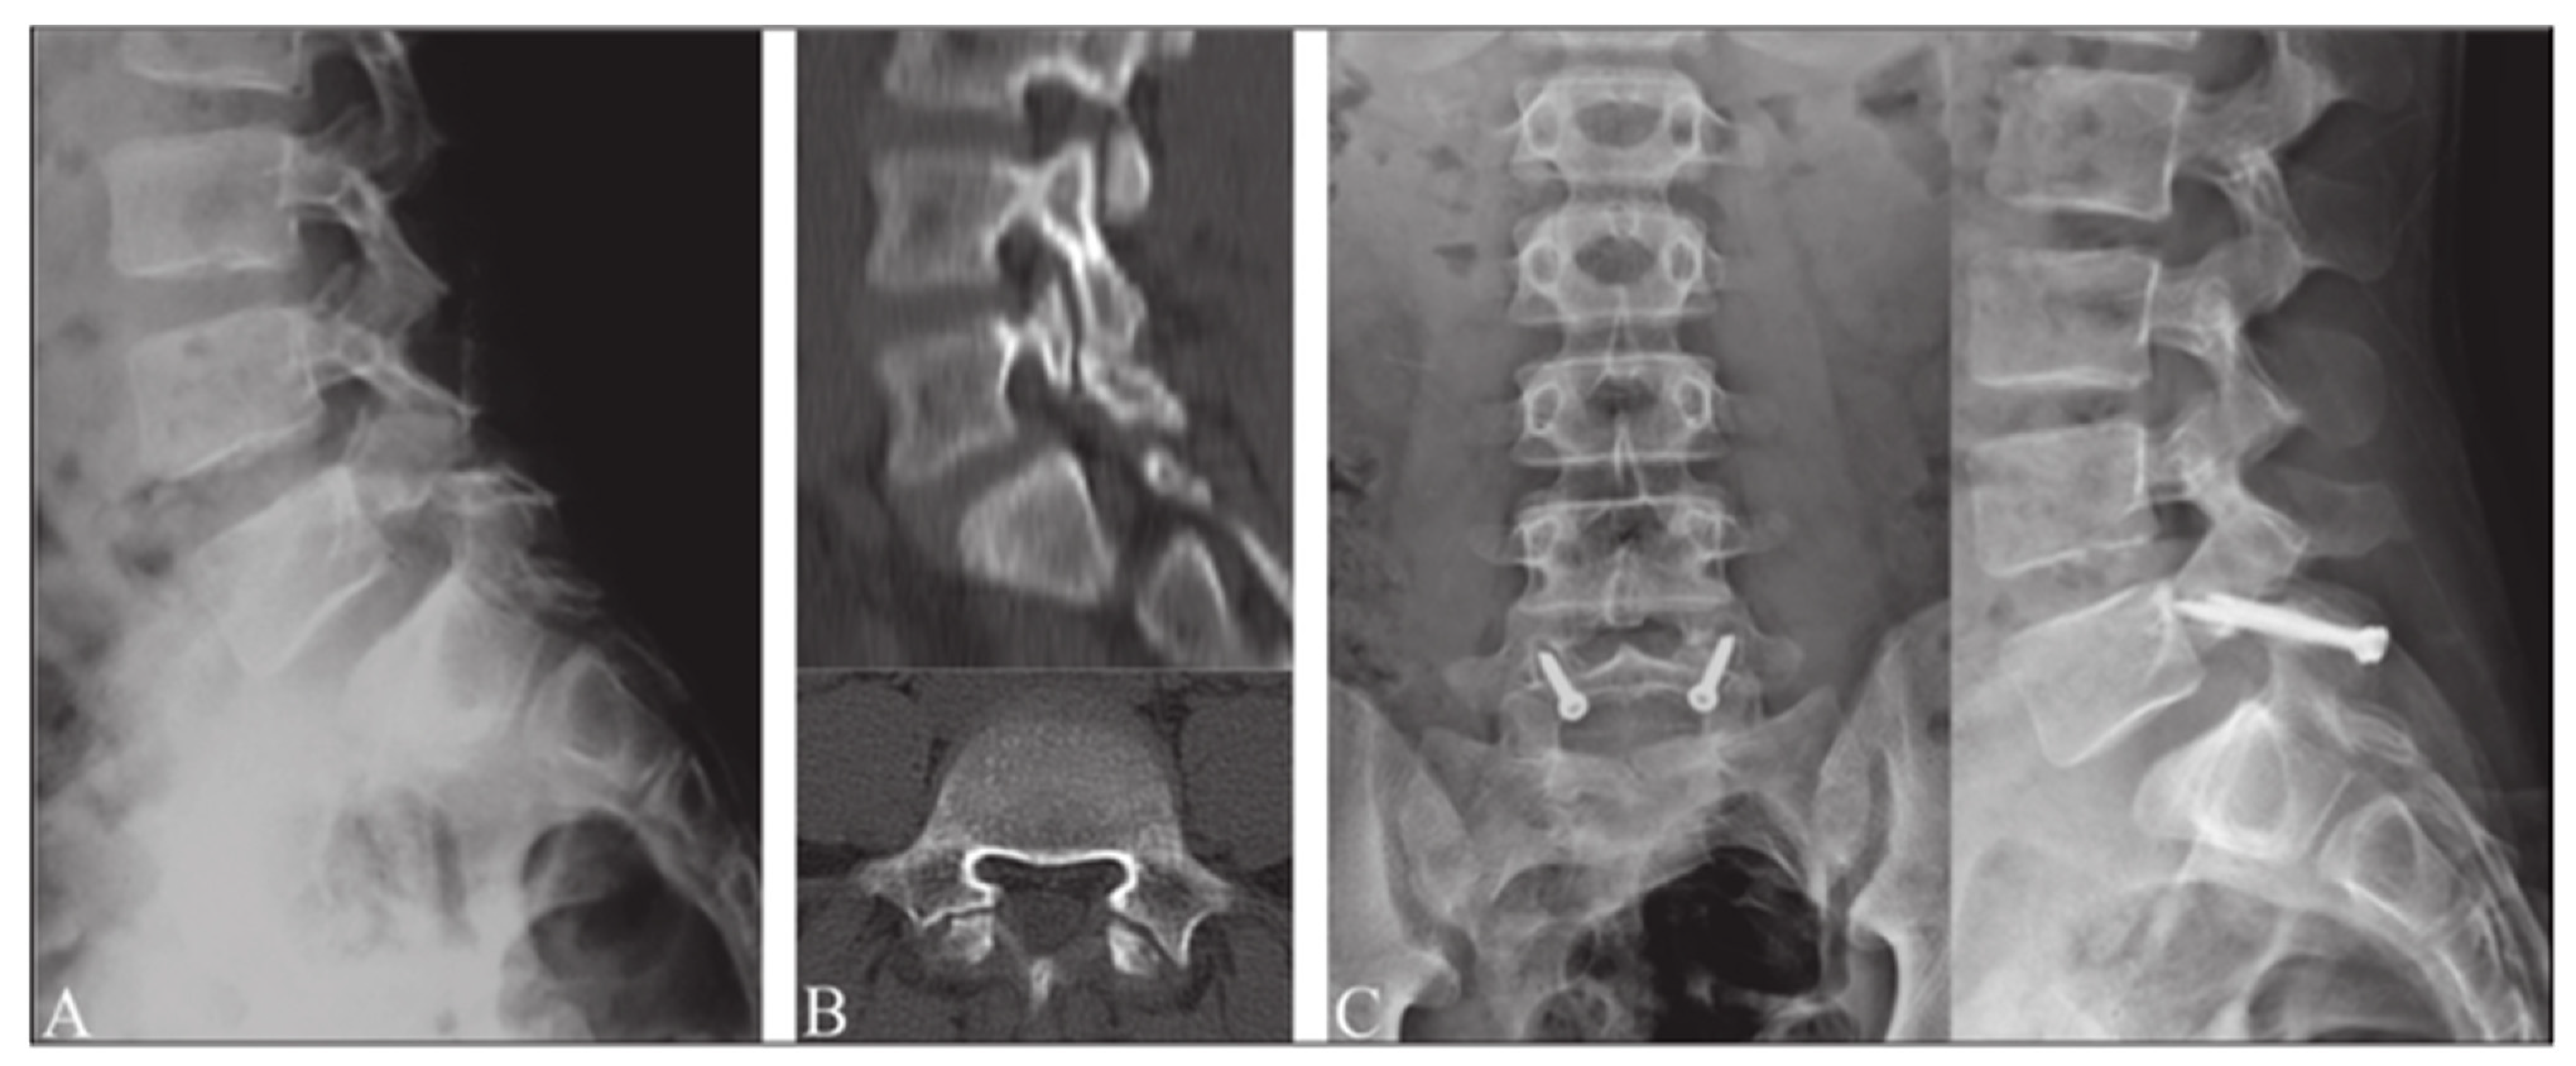

- Widi, G.A.; Williams, S.K.; Levi, A.D. Minimally invasive direct repair of bilateral lumbar spine pars defects in athletes. Case Rep. Med. 2013, 2013, 659078. [Google Scholar] [CrossRef]

- Ghobrial, G.M.; Crandall, K.M.; Lau, A.; Williams, S.K.; Levi, A.D. Minimally invasive direct pars repair with cannulated screws and recombinant human bone morphogenetic protein: Case series and review of the literature. Neurosurg. Focus 2017, 43, E6. [Google Scholar] [CrossRef] [PubMed]